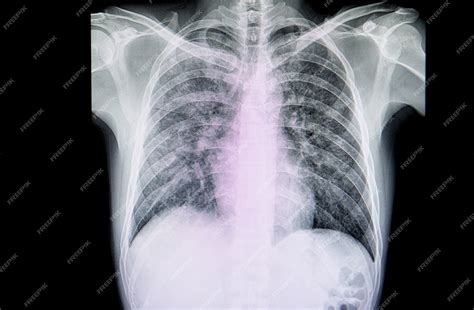

- Radiografía o TAC de tórax: Permiten observar alteraciones pulmonares o cardíacas que puedan ser la causa de la cianosis.